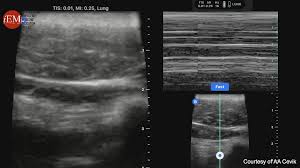

경동맥 초음파 검사는 고주파 초음파를 사용하여 목의 경동맥 혈관을 영상으로 확인하는 검사입니다. 혈관 내벽 두께, 혈류 흐름, 좁아진 정도 등을 실시간으로 볼 수 있으며, 조영제나 방사선 노출이 없어 안전합니다. 검사 시간은 약 20~30분 정도 소요됩니다.

환자는 검사 침대에 누운 후, 목에 젤을 바르고 초음파 탐촉자를 대어 경동맥을 관찰합니다.